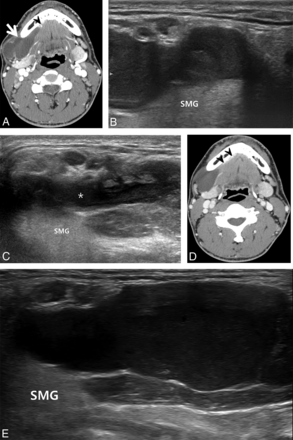

A 19-year-old man with a plunging ranula in the right submandibular space developed 1 month previously. A and B, Pretreatment contrast-enhanced axial CT images. A, Axial CT image shows a well-defined cystic mass in the right submandibular (thick arrow) space. B, Another CT image demonstrates the cystic mass continuing into the sublingual space (thin arrow), showing direct contact with bilateral sublingual glands (arrowheads). C, Pretreatment oblique sonogram shows a fluid collection with internal debris in the right submandibular space (arrows). D, Sonogram 1 month after 2 sessions of ethanol ablation in the same plane as C shows complete disappearance of the ranula in the submandibular space. E, A sonogram 12 months after D in the same plane shows complete disappearance of the ranula in the submandibular and sublingual spaces. SMG indicates submandibular gland; M, mylohyoid muscle; D, anterior belly of the digastric muscle.